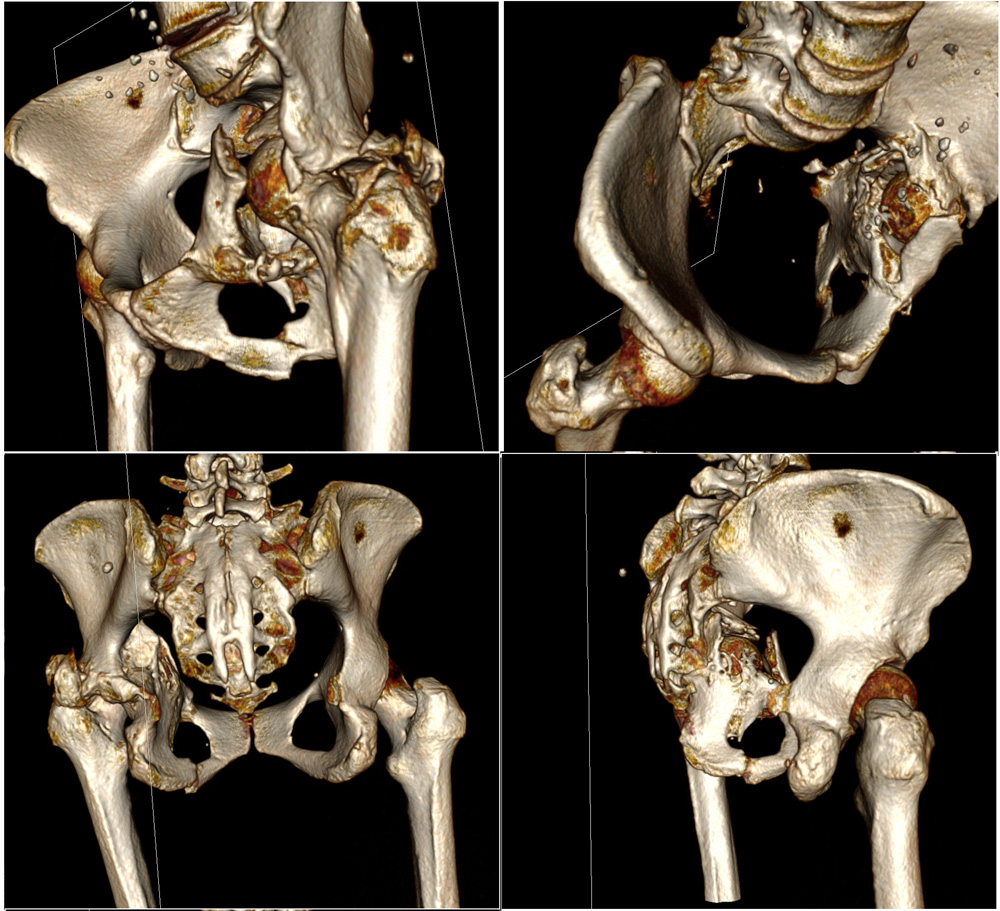

Женщина, 62 г, ДТП 25.11.2014. Перелом ВВ, лонной и седалищной костей с нарушением непрерывности тазового кольца, частичный разрыв КПС, гнойная рана бедра, все слева. Лечилась консервативно, вытяжение не удалось, полное заживление раны через 5 мес. Левая конечность неопороспособна, но явных признаков некроза головки нет. Пытаться выполнить остеосинтез при сроках 8 месяцев абсолютно нецелесообразно? Если неизбежно эндопротезировать, то поделитесь мнениями о предпочтительной тактике: как лучше поступить с передней колонной, сделать пластику ВВ аутокостью, необходимо ли кольцо Бурш-Шнайдера/Октопус?

Перелом похож на Т-образный или anterior column posterior hemi-transverse. Здесь передная стенка отошла на несколько сантиметров и с этим нарушено целостность кольца в вертлужной впадине. Небольшие смещения в задней колонне или в стенке, которых можно фиксировать во время протезирования, особых проблем не вызывают, а передная колонна-куда приходится основная нагрузка не выдерживает нагрузку и осложняются расшатыванием!

Усиливающее кольца Мюллера/Бурша-Шнайдера в основном сидит в задней колонне, а передная колонна остается свободной без опоры. В большинстве реконструкцонные специалисты обращают внимание на правила "вначале создание непрерывности кольца", которое влияет на долговечность артропластики.

Но, в данном варианте, еще имеется неполный разрыв крестцово-подвздошного сочленения и если не фиксировать, тогда возможно возникновение болей после артропластики и тогда трудно дифференцировать источник: из сустава или из крестцово-подвздошного сочленения?

По моему, гарантировать успех можно после профилактической фиксации КП сочленения и после создания стабильности передней колонны. Некоторые, после стабилизации вертлужной впадины чувствует намного лучше, и при конгруентной головке, возможно нет смысла спешить с заменой сустава? А операция в колонне дасть возможность оценить качество покрытия хрящом головки бедра и решить вопрос, замена сустава одномоментно или поэтапно!